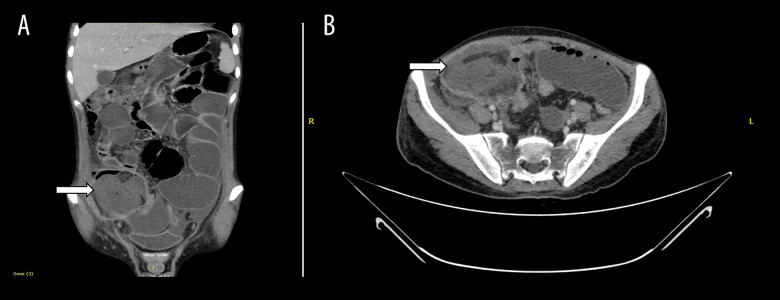

BACKGROUND Gastrointestinal mucormycosis is an underrecognized and underreported fungal infection with a high mortality rate. Diagnosis is often confounded by a non-specific constellation of signs and symptoms. We present a case of neutropenic colitis and ileocecal perforation secondary to gastrointestinal mucormycosis. CASE REPORT The patient was a 19-year-old man recently diagnosed with B-cell acute lymphoblastic leukemia, on active chemotherapy. He presented with abdominal pain and tenderness, and a contrast-enhanced CT revealed neutropenic colitis. Despite broad-spectrum antibiotics, his condition worsened, prompting reassessment. Follow-up CT showed bowel ischemia and a pelvic collection. He underwent an emergency laparotomy, which revealed destruction of the anterior cecal wall and detachment from the terminal ileum and ascending colon. Ileocecal resection was performed and histopathologic examination demonstrated angioinvasive fungal elements consistent with Mucor spp. He was diagnosed with gastrointestinal mucormycosis and promptly started on amphotericin intravenously. He improved over the next 2 weeks and was discharged with a plan to continue his 6-week course as an outpatient, followed by oral posaconazole maintenance therapy. Several weeks later, his infection relapsed secondary to non-compliance. He underwent repeat surgical debridement and antimicrobial therapy was restarted with intravenous amphotericin and Isavuconazole. He successfully completed 6 weeks of treatment and was transitioned to oral Isavuconazole prophylaxis. He remained stable and relapse-free at 6 months following his second procedure. CONCLUSIONS The case highlights the importance of early recognition of patients at risk for this infection, maintaining a high index of suspicion, and employing aggressive medical and surgical management strategies to avoid mortality.